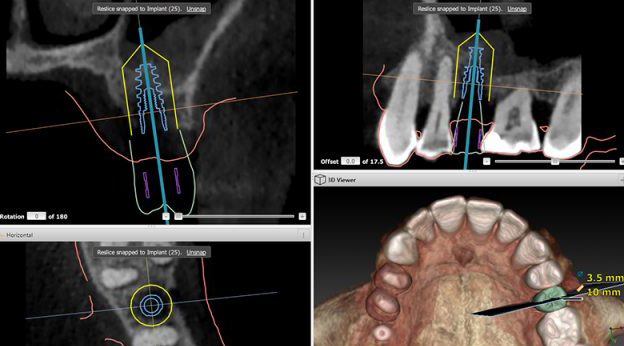

Notre cabinet dentaire est équipé d’un Système de numérisation intra-orale pour le confort de nos patients. C’est un véritable outil de diagnostic et de prise d’empreinte numérique.

Un co-diagnostic avec le patient par une visualisation en 3D sur un écran déporté.

Une prise d’empreinte numérique des dents, plus précise et plus rapide qu’une prise d’empreinte réalisée avec de la pâte en bouche.

D’envoyer des fichiers numériques au laboratoire pour concevoir sur ordinateur la futur prothèse dentaire.